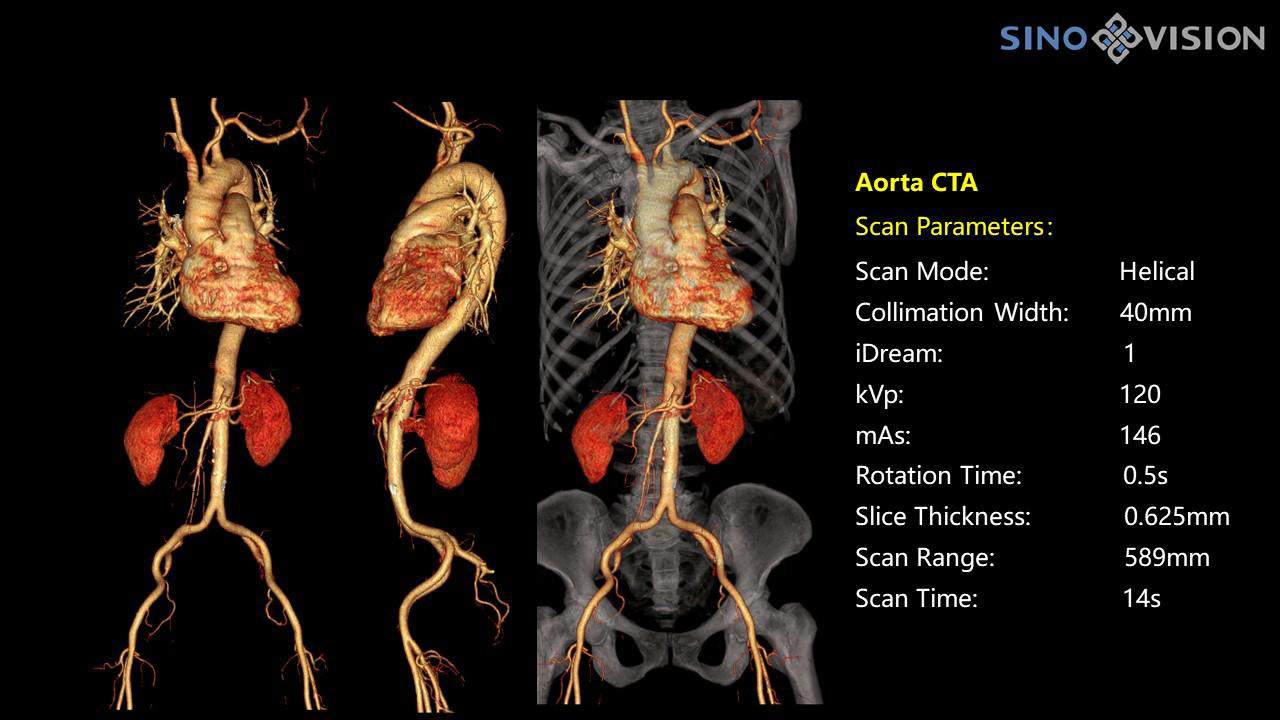

InsitumCT 768 является вершиной нового поколения широкоапертурных широкополосных компьютерных томографов. Этот КТ-сканер обеспечивает 128 срезов КТ при апертуре 76 см, увеличивая производительность визуализации до 21 л/см, способствуя точной диагностике и лечению заболеваний и значительно улучшая клинические характеристики и масштабируемость. Обеспечивает получение изображений высокого разрешения при низкой дозе облучения.

Компьютерный томограф Insitum CT 768 – старшая модель в линейке SinoVision Insitum. Еще более быстрый и еще более мощный, он значительно повышает пропускную способность кабинета КТ, обеспечивая при этом высококачественные исследования даже в самых сложных случаях практически во всех областях, включая кардиологию, исследования сосудистой системы, онкологию. Имеет специализированный педиатрический протокол исследования, минимализирующий лучевую нагрузку на ребенка.

Специализированная технология RTF позволяет уменьшать артефакты движения сердца, обеспечивая максимально точное клиническое изображение.

- Количество срезов: 128

- Толщина среза: 0.625 мм

Характеристики сканирования

- Минимальное время одного оборота рентгеновской трубки: От 0.37 до 2 сек

- Коронарный анализ

- Общий анализа сосудов на основе серии данных КТ